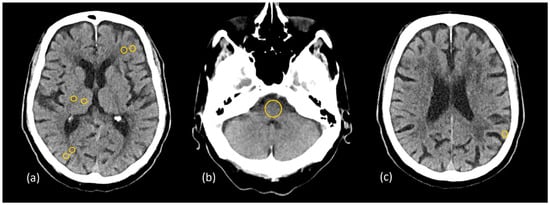

Figure 3.

Region of interest (ROI) placement on the cross-sectional phantom images: dark red ROIs represent Hounsfield units (HU) and standard deviation (SD) measurements in gray matter–white matter pairs in the frontal and parietal lobes at the level of the basal ganglia (a,b), and green ROIs represent SD measurements in the subcalvarial region and the posterior fossa (a,c).

A methodology similar to that described by Weinman [29], Pomerantz [35], and Kim [25] was applied for quantitative image quality analysis. A fixed circular 25 mm2 region of interest (ROI) was placed at four pairs of identical GM and WM locations in the frontal and parietal lobes at the level of the basal ganglia (Figure 3), where the mean and standard deviation (SD) of the attenuation in Hounsfield units (HU) were measured. Posterior fossa and subcalvarial beam hardening artifacts were quantified as the mean SD of three measurements within fixed circular 200 mm2 and 25 mm2 ROIs, placed at the level of the midbrain and in the brain parenchyma near the skull, respectively (Figure 3). Noise values (SD) for SCA and PFAI were averaged over three measurements to ensure more precise assessment. The CNR of each GM–WM pair was calculated using the following expression:

and the results were averaged across the four regions for comparison.